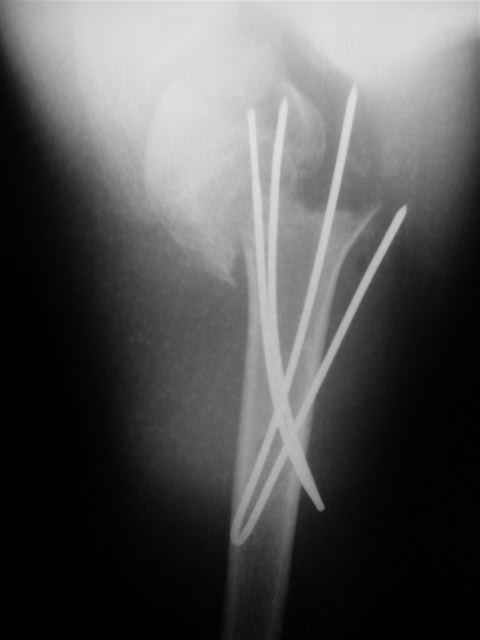

Клинические снимки - 3 недели после операции

с уважением М. Беренштейн

Посылаю послеоперационные Рг граммы.

Всего Доброго,

Отправитель: Alexander Chelnokov 02 Декабрь 2004, 19:21

Поздравляю, получилось просто замечательно. Если можно, расскажи чуть подробнее, как делали - как вправляли, как вводили спицы, поворачивали ли их?